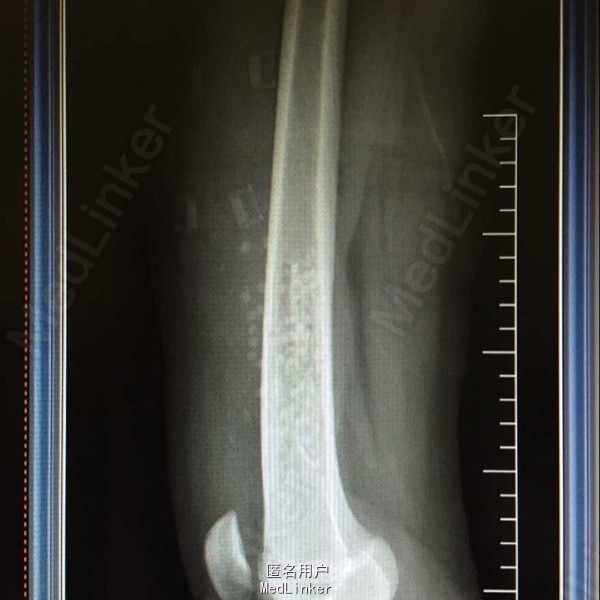

患者,女,13岁,长时间走路后出现右股部下段疼痛,呈间断性,偶然有夜间痛

CT结果为右侧股骨皮质内可见一条片状骨质缺损区,呈软组织样密度影,范围约12*8*48cm,其边缘可见条状硬化,病变长轴与股骨长轴一致,考虑纤维性骨皮质破损,X线示:右股骨下端距关节上方约6cm处可见骨质密度减低影,成分房状,边界可见钙化影。

术后病理报告结为:”右股骨下段“小块增生纤维组织伴含铁血黄素沉着,片内提示结合临床及影像学考虑,干骺端纤维缺损或非骨化纤维瘤。